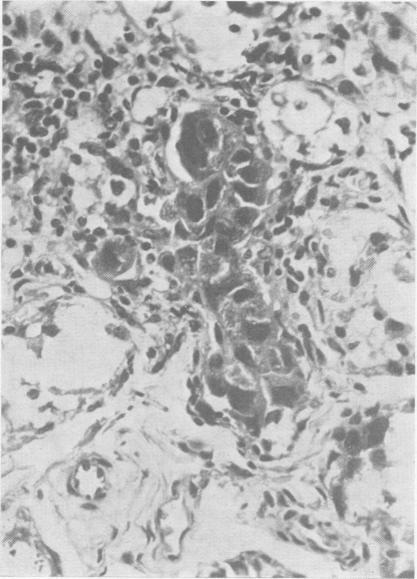

Inclusion disease in childhood.

Arch Dis Child. 1951 Dec;26(130):588-600. doi: 10.1136/adc.26.130.588.